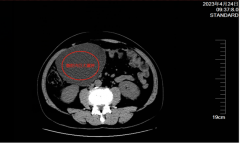

男子患肠系膜肿瘤肚子疼4天

男子患肠系膜肿瘤肚子疼4天 东莞的骆先生今年55岁,4月23日到谢岗医院(市人民医院谢岗院区)治疗,他4天...